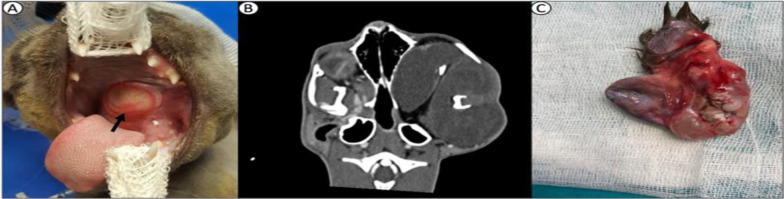

Case description: In this report, a 5-month-old kitten was brought to the clinic with the complaint of difficulty breathing, food intake, and oropharyngeal mass. In clinical examination, there was a large mass, protruding from the localization included left buccal mucosa, soft palate, and extending into the oropharynx but no cranial extension was observed in CT scans. The mass was completely resected. Macroscopically, the mass measured 4.5 × 6.5 cm2 and contained solid and cystic areas associated with soft and hard tissue components.

Findings/treatment and outcome: Histopathology revealed an extragonadal solid-cystic (grade 0) oropharyngeal mature teratoma containing structures from endoderm, mesoderm, and ectoderm. After an 8-month follow-up control period, no signs of recurrence were observed.

Conclusion: The case was deemed worthy of being presented with its clinical, radiological, and pathological findings, and complete resection was curative for mature teratoma.